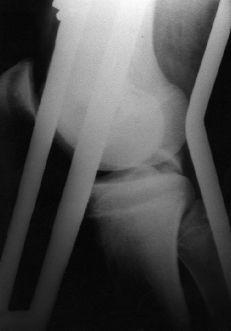

Figura 2. Niño de 15 años de edad con fractura avulsión del LCP y fractura asociada de la diáfisis del fémur. A: Radiografía preoperatoria. B: Radiografía a los 6 meses de evolución.